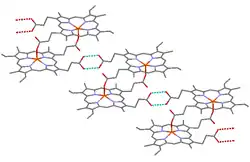

β-Hematin crystals are made of dimers of hematin molecules that are, in turn, joined together by hydrogen bonds to form larger structures. In these dimers, an iron-oxygen coordinate bond links the central iron of one hematin to the oxygen of the carboxylate side-chain of the adjacent hematin. These reciprocal iron–oxygen bonds are highly unusual and have not been observed in any other porphyrin dimer. β-Hematin can be either a cyclic dimer or a linear polymer,[31] a polymeric form has never been found in hemozoin, disproving the widely held idea that hemozoin is produced by the enzyme heme-polymerase.[32]

The best-understood examples of such hematin biocrystallization inhibitors are quinoline drugs such as chloroquine and mefloquine. These drugs bind to both free heme and hemozoin crystals,[39] and therefore block the addition of new heme units onto the growing crystals. The small, most rapidly growing face is the face to which inhibitors are believed to bind.[40][41]